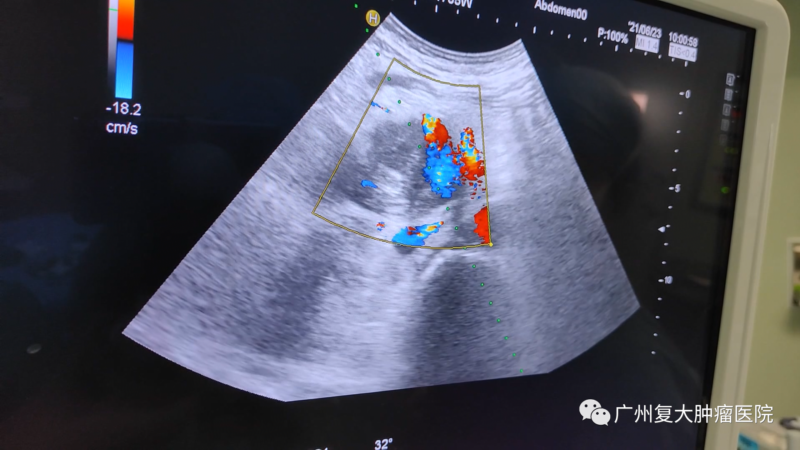

针对刘叔的病情,我院牛立志院长为他实行胰腺及肝脏转移瘤穿刺活检+胰腺及肝脏转移瘤纳米刀消融术。在超声+CT引导下,全程监测、设计布针路线、避开重要的血管,将“纳米刀”精准植入肿瘤,以达到减轻肿瘤负荷,减缓疾病进展的效果。

影像(如超声、CT等)引导下经皮纳米刀消融,无需开腹,只需几个针尖大小的小孔,达到杀灭肿瘤的效果,减轻病人痛苦。在影像设备的辅助下,可以对纳米刀探针的定位、标靶区域的消融过程以及最终消融区的大小进行实时监控,且影像中消融区边界的精确度可与组织学上的精确度相媲美。另外,实时监测还可以让医生观察到消融区周围组织的变化,从而推断出并发症出现的可能性,保障病人的安全以及有助于其术后快速恢复。